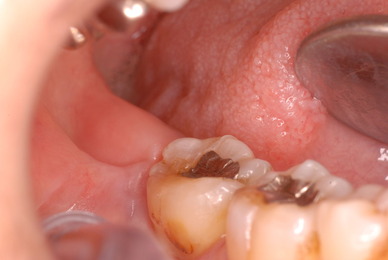

神経が死んでしまった歯は脆いのです。

重症の歯周病で削って上の歯とぶつからないようにしていた歯ですが

いつの間にか神経が死に歯の中が腐っていたようです。

それでヒビが入り割れてしまいました。